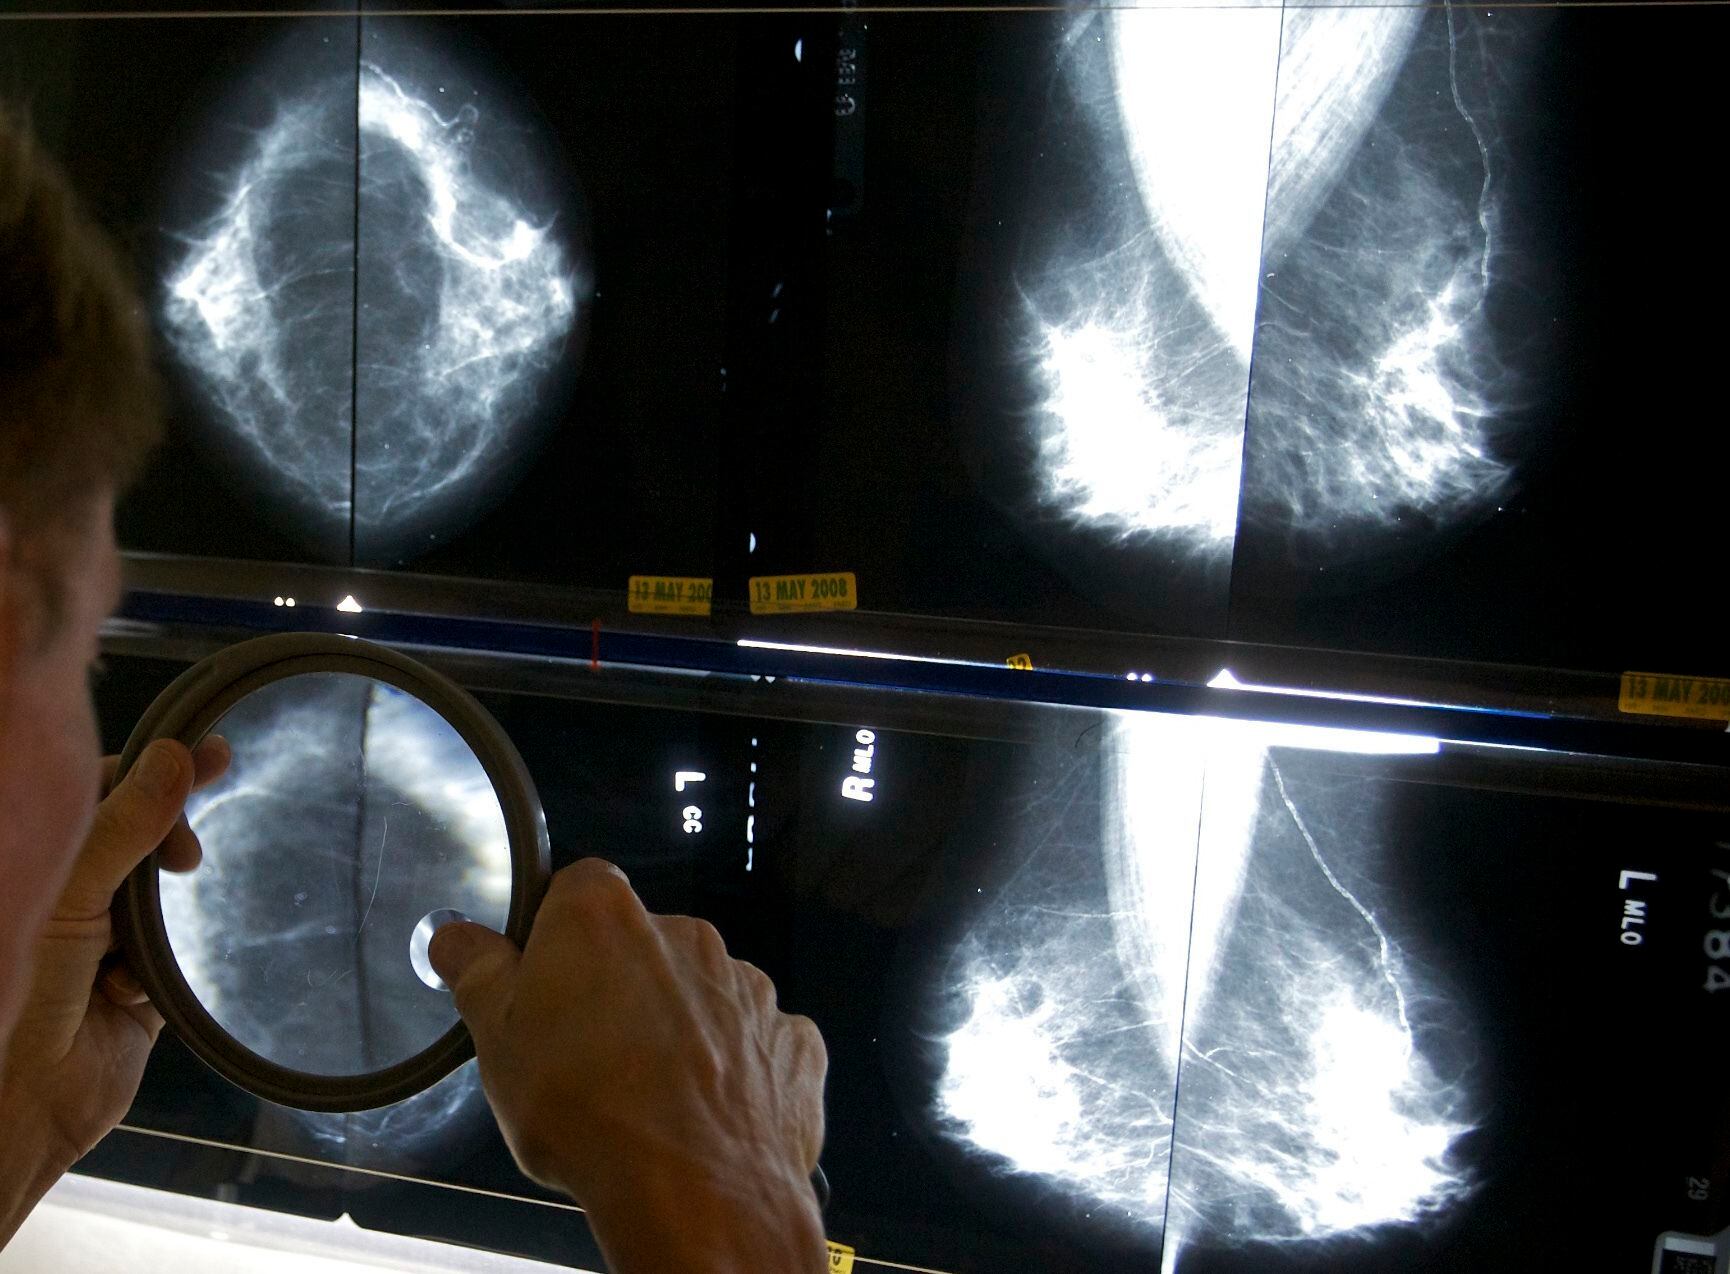

Es a partir de los 40 años cuando se recomienda que las mujeres anualmente se realicen una mastografía o mamografía, un estudio de 15 minutos con rayos equis en las glándulas mamarias para detectar cambios o anomalías en el tejido de los senos. El IMSS explica que a cada mama se le toman dos radiografías (una lateral y otra de arriba hacia abajo), las cuales causan molestias tolerables.

Si el estudio sale negativo, se pide a la mujer volver al año siguiente, pero en caso de que haya un resultado anormal, se realiza otra mamografía para abundar en detalles sobre la anomalía. Después de que ya está el diagnóstico, es importante comenzar a atenderse cuanto antes, pues cuando se atiende a tiempo, las posibilidades de cura son de entre 75 y 85 por ciento, según datos de la Fundación Cima.

La mastografía es el estudio que puede ayudar a detectar a tiempo el cáncer de mama. Foto: AP/Damian Dovarganes, Archivo

La mastografía es el estudio que puede ayudar a detectar a tiempo el cáncer de mama. Foto: AP/Damian Dovarganes, Archivo